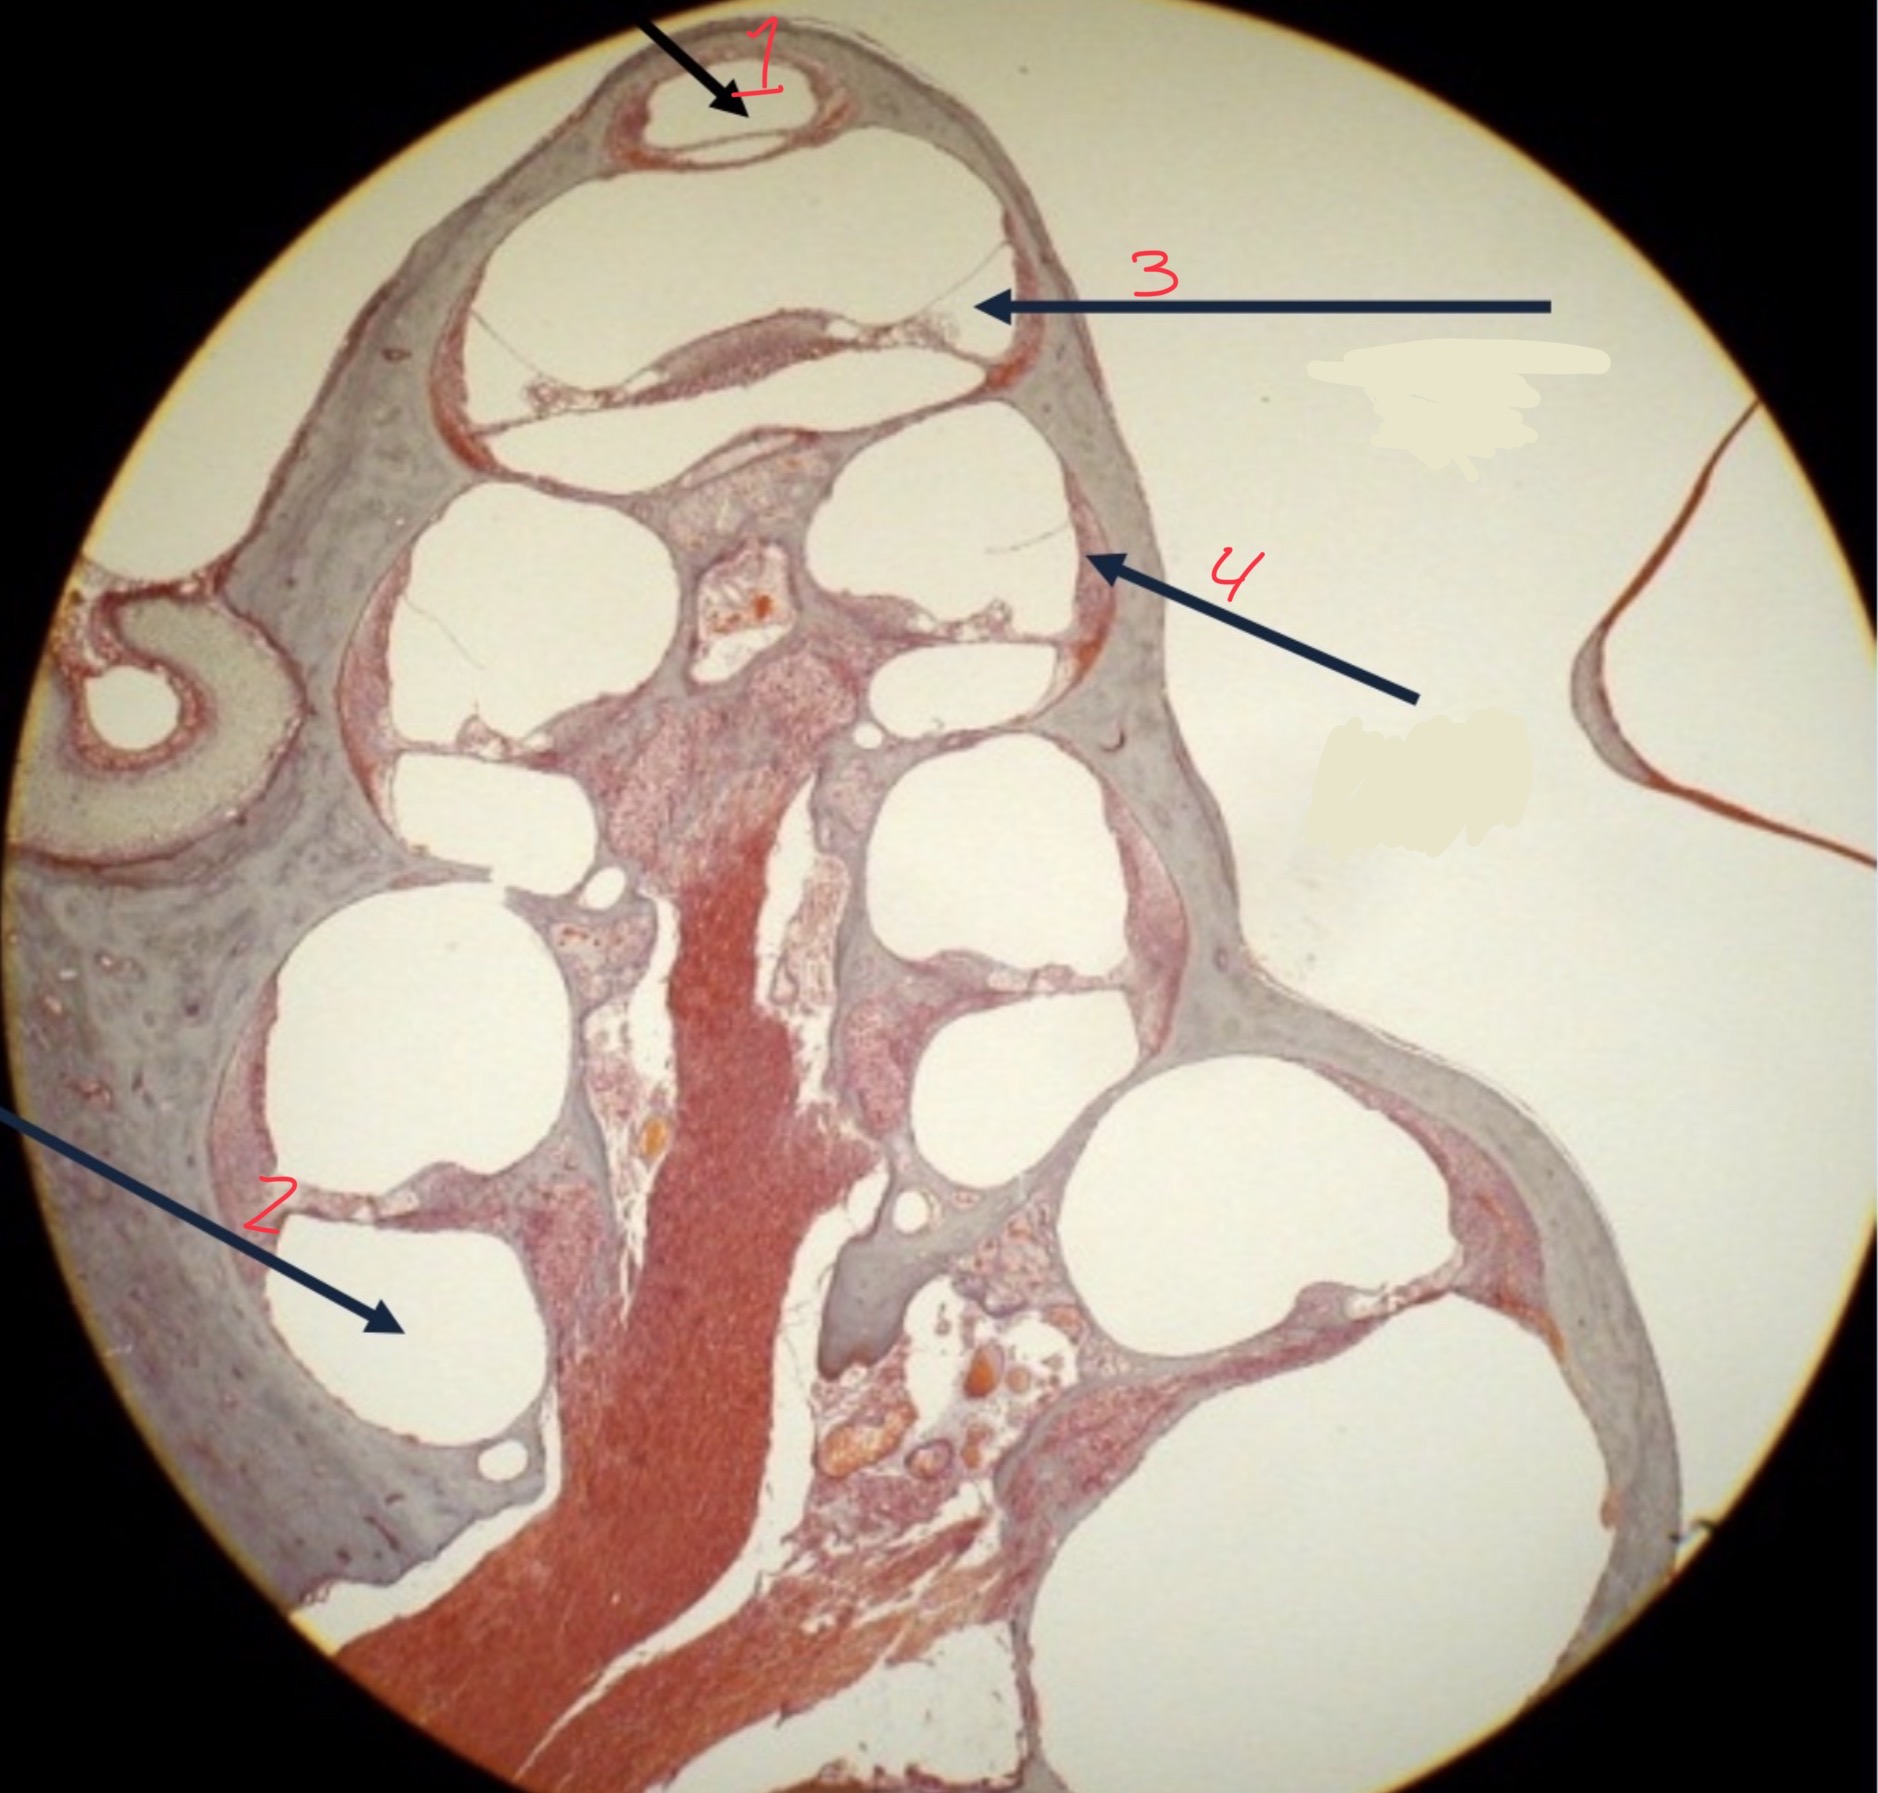

1

Helicotrema

2

Scala tympani

3

Cochlear duct

4

Basilar membrane